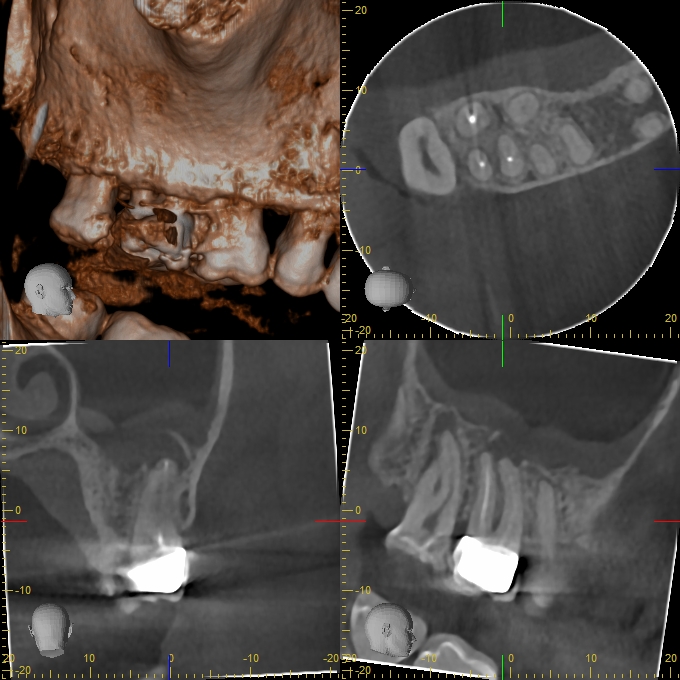

XYZView_20140429_111904

680 × 680

2D vs. 3D (XXVII)